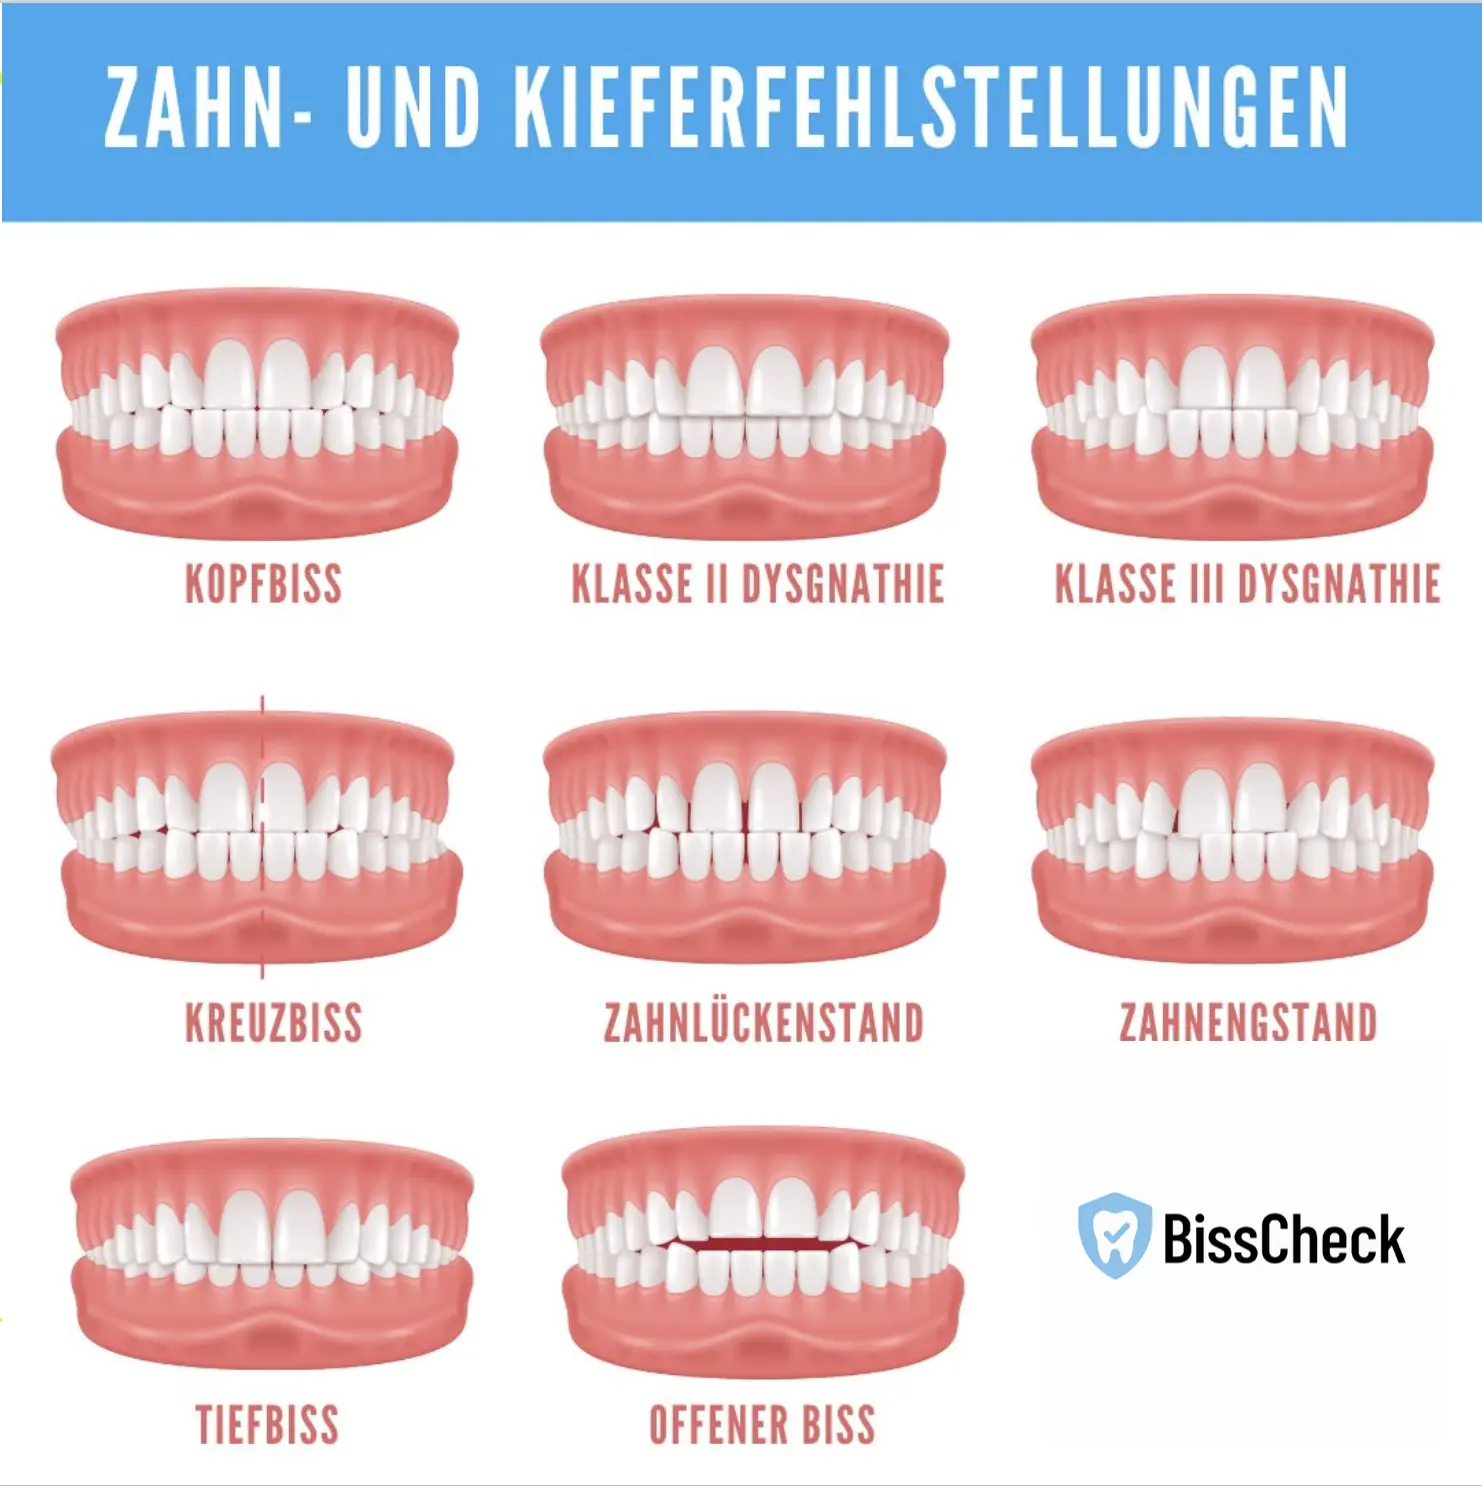

Zu den häufigsten Zahnfehlstellungen zählen Kopfbiss, Kreuzbiss, Tiefbiss, offener Biss sowie Dysgnathien und Eng- oder Lückenstände. Mit der digitalen Bissanalyse von BissCheck können diese frühzeitig erkannt werden.

Zahnfehlstellungen gehören zu den häufigsten Problemen in der Zahnmedizin. Ob Überbiss, Kreuzbiss oder Engstand – sie beeinflussen nicht nur das Lächeln, sondern auch Kauen, Sprechen und langfristig die Zahngesundheit. In diesem umfassenden Ratgeber erfahren Sie alles über Ursachen, Arten, Folgen und moderne Behandlungsmethoden. Zudem zeigen wir, wie Sie mit der kostenlosen digitalen Bissanalyse von BissCheck schnell und anonym eine fachärztlich fundierte Ersteinschätzung erhalten können.

Arten der Zahnfehlstellungen

Engstand / Platzmangel

Kreuzbiss

Offener Biss

Zahnlücken (Diastema)

Welche Arten von Zahnfehlstellungen gibt es?

Zu den häufigsten gehören:

Überbiss (Distalbiss)

Unterbiss (Progenie/Vorbiss)

Tiefbiss

Kreuzbiss

Offener Biss

Engstand

Lückenstand (Diastema)

Retinierte oder verlagerte Zähne

Hyperdontie (überzählige Zähne)

Oft treten mehrere Formen gleichzeitig auf.